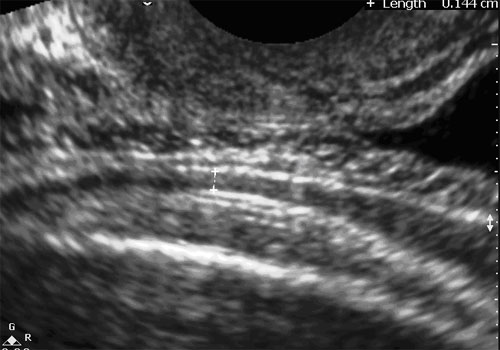

6) MEASUREMENT IN FIRST TRIMESTER :

Picture shows measurement of the thickness of lower uterine segment in the 1st trimester using a 7.5 MHz. transvaginal probe.

The cervix and lower uterine segment were visualized in the sagittal plane. The thickness of the anterior wall of the lower uterine segment and the total thickness of the lower uterine segment were measured at the level of the internal os ( placing the calipers at the edge of the internal os and the outer edge of the myometrium).